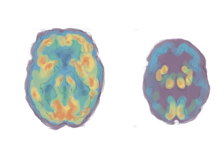

Le projet Dynamo, mené par Stanley Durrleman et le neurologue Harald Hampel, permettrait de créer un modèle numérique de l’évolution du cerveau dans la maladie d’Alzheimer.

En fournissant ce type d’outil personnalisé, il serait envisageable de prédire, réduire voire éviter la progression de la maladie dès les premiers oublis. Le tout sur une simple visite chez un neurologue.